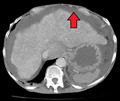

Imaging

Ultrasound is routinely used in the evaluation of cirrhosis. It may show a small and nodular liver in advanced cirrhosis along with increased echogenicity with irregular appearing areas. Other liver findings suggestive of cirrhosis in imaging are an enlarged caudate lobe, widening of the fissures and enlargement of the spleen. An enlarged spleen (splenomegaly), which normally measures less than 11–12 cm in adults, can be seen and may suggest underlying portal hypertension. Ultrasound may also screen for hepatocellular carcinoma, portal hypertension, and Budd-Chiari syndrome (by assessing flow in the hepatic vein). An increased portal vein pulsatility is an indicator of cirrhosis, but may also be caused by an increased right atrial pressure.[37] Portal vein pulsatility can be quantified by pulsatility indices (PI), where an index above a certain cutoff indicates pathology:

Cirrhosis is diagnosed with a variety of elastography techniques. Because a cirrhotic liver is generally stiffer than a healthy one, imaging the liver's stiffness can give diagnostic information about the location and severity of cirrhosis. Techniques used include transient elastography, acoustic radiation force impulse imaging, supersonic shear imaging and magnetic resonance elastography. Compared to a biopsy, elastography can sample a much larger area and is painless. It shows a reasonable correlation with the severity of cirrhosis.[40]

Other tests performed in particular circumstances include abdominal CT and liver/bile duct MRI (MRCP).